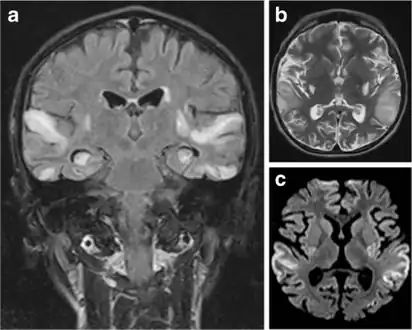

MRI: Multifocal infarct-like cortical areas in different stages of ischemic evolution, areas that do not conform to any known vascular territory. Initial lesions often occur in the occipital or parietal lobes with eventual involvement of the cerebellum, cerebral cortex, basal ganglia, and thalamus.